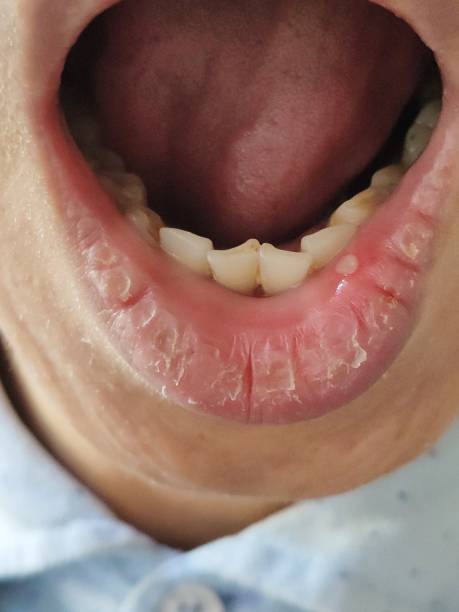

구내염의 원인은 여러 가지를 이야기하지만 스트레스, 호르몬 변화, 영양 부족 등 다양한 원인에서 기인하는 것으로 알려져 있습니다. 과로시 음식을 먹거나 이를 닦을 때 입안이 거칠고 아플 수 있고,. 음식을 씹어서 입이 다치는 경우도 비슷한 증상을 보이며 입에서 흘러나오는 침이 줄어들어서 발생합니다. 구내염은 흰색의 타원형 모양을 하고 있는 구강 점막의 염증이나 흉터로 인한 염증 반응으로 생기는데 이를 예방하기 위한 다양한 원인과 치료하는 방법을 알아보겠습니다.

구내염 원인이네 번째로는 구강내 자극을 이야기할 수 있습니다. 이유는 음식을 먹는 과정에서 치아에 의하여 잇몸 부분을 뜽어 점막에 상처가 생긴다거나 잘못 맞물려 구내염이 발생할 수 있습니다.